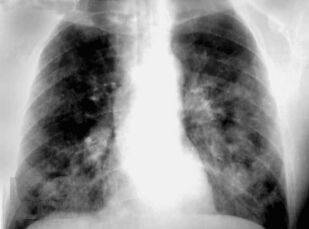

Книга профессора П.В. Власова посвящена современному состоянию лучевой диагностики заболеваний органов грудной полости. Она является первой в отечественной литературе крупной работой, в которой освещена диагностика заболеваний органов грудной полости: острых пневмоний и плеврита, хронических неспецифических заболеваний легких, туберкулеза органов дыхания, рака легкого, опухолей плевры, диффузных и диссеминированных процессов легких, опухолей и кист средостения. Все вопросы рассматриваются с учетом самых современных взглядов на патогенез и диагностику заболеваний.

Большим достоинством книги является комплексный подход к диагностике заболеваний. Наряду с традиционными методами ретгенологического исследования, такими как рентгенография и линейная томография, в книге получили полное освещение роль и место в современном комплексе диагностических средств такие методы, как компьютерная томография и ультрасонография, значительно расширившие возможности диагностики заболеваний.